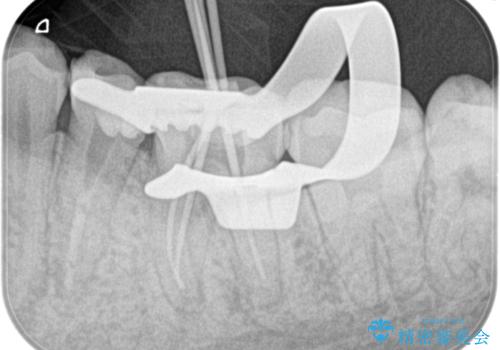

精密根管治療。大臼歯イニシャルケース

- 奥歯がズキズキ痛いことを主訴に来院されました。

検査の結果、診断を症候性不可逆性歯髄炎、症候性根尖性歯周炎とし抜髄を行っております。

根管充填はCWCTにて行なっております。

根管形成はマルテンサイト相を有するNi-Tiロータリーファイル(NEX MS)使用。